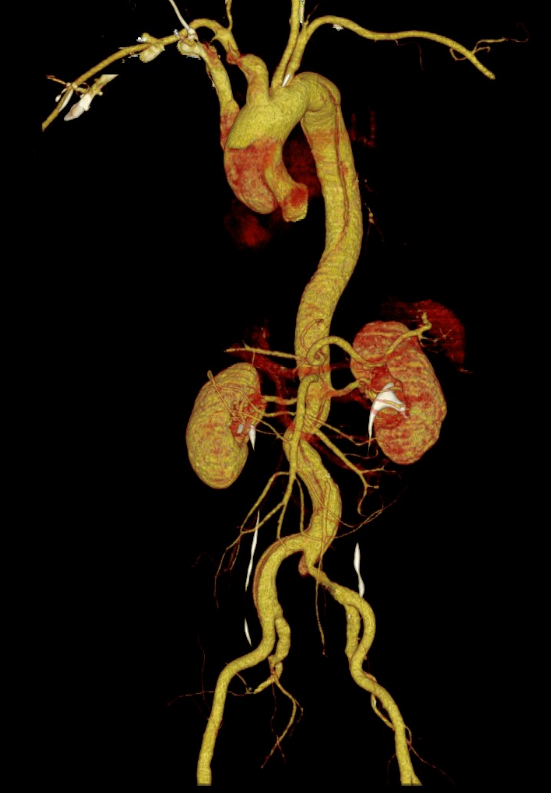

△CTA教导主动脉夹层A型

更毒手的是,患者的A型主动脉夹层,这种夹层扯破不仅发生在胸腔的大血管内,还进取推广,累及了通往大脑的右侧颈动脉整段,导致右侧大脑半球出现分水岭脑梗死,脑灌输严重减低。

患者抵达后,急诊团队马上运行危重症救治经过,立即完善头颈CTA及颅脑MR查验,着力进一步明确:主动脉夹层;右颈总动脉、右颈内动脉长节段未见显影,探讨夹层累及或假腔血栓变成;右侧大脑半球分水岭脑梗死,灌输减低。

△头颈CTA教导右颈总动脉长节段未见显影,探讨夹层累及或假腔血栓变成。